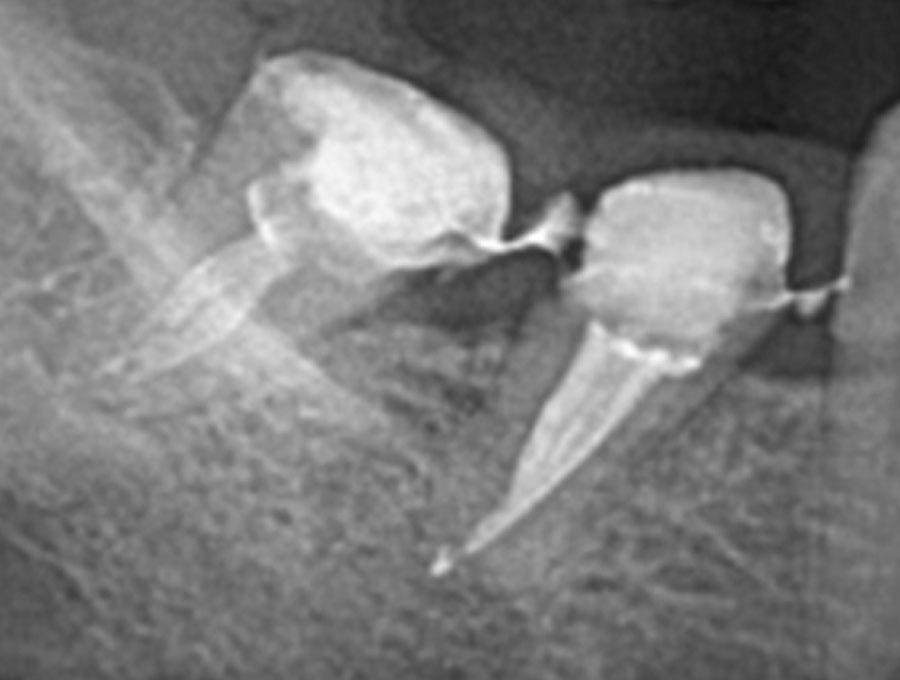

Αρχική εικόνα δοντιού

Τελική εικόνα δοντιού μετά από θεραπεία